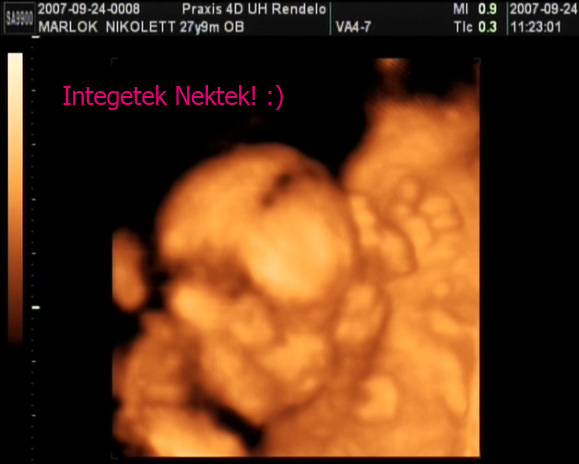

ui: ma vagyunk 13hetesek, ujjéééé